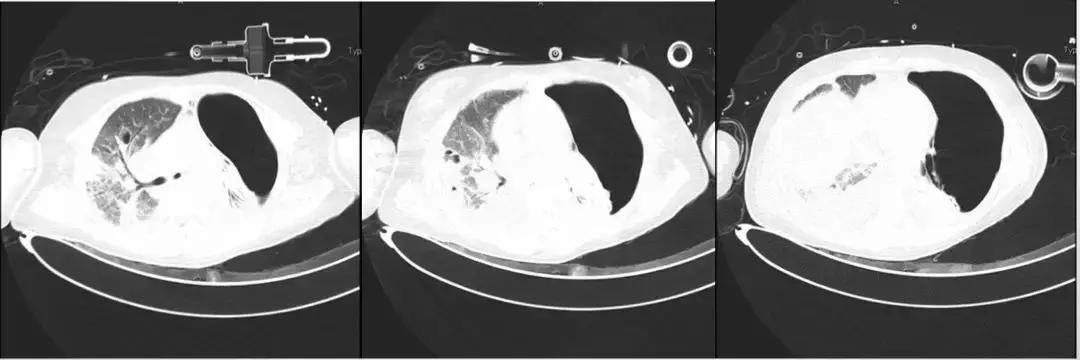

*影像学显著进展

7月10日:

发热持续、肺部病变加重,问题何在?如何解决?

*影像学仍持续变化:

左侧胸腔病变为肺大泡?气胸?如何处理?药物是否需要调整?